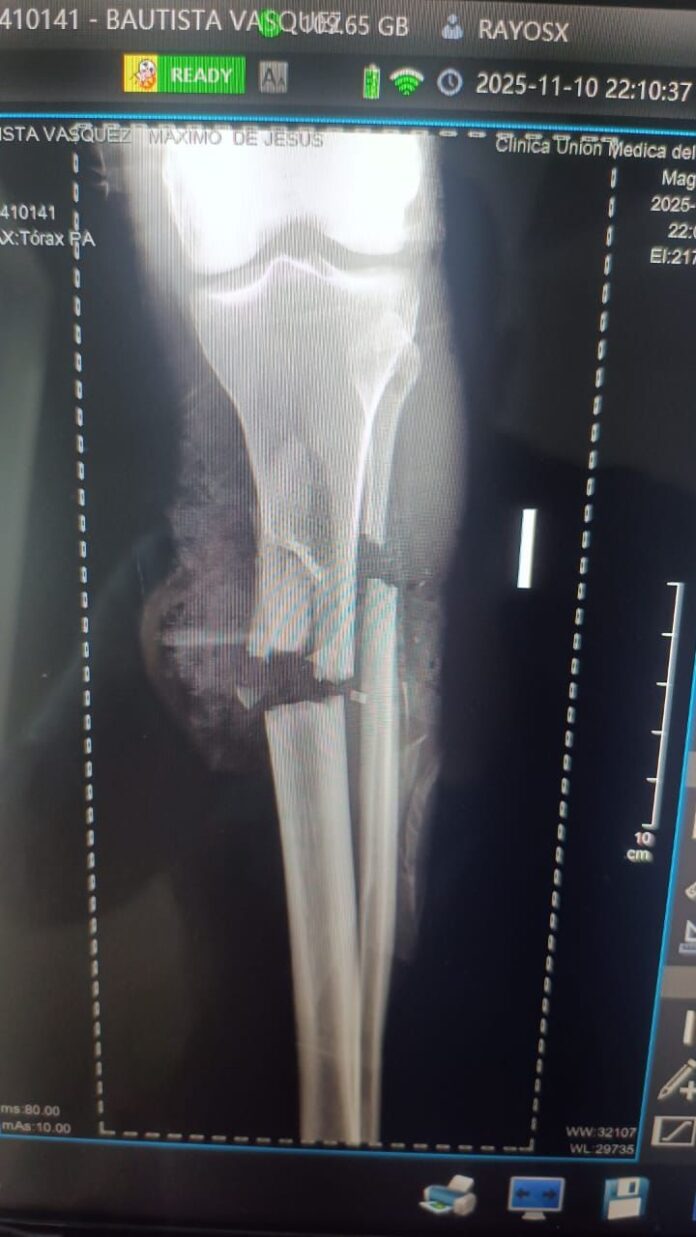

Como consecuencia directa de la acción violenta, la actual pareja de la mujer, identificada como Máximo de Jesús Bautista Vásquez, sufrió afectaciones de extrema gravedad. Entre ellas se informó una amputación en la pierna izquierda y una fractura severa en la pierna derecha, situación que lo mantiene en condición crítica y bajo supervisión constante debido a la complejidad del cuadro clínico que presenta luego de lo ocurrido.

Bautista Vásquez se encuentra ingresado en la Unidad de Cuidados Intensivos de la Clínica Unión Médica, donde recibe atención especializada de parte del personal médico. Los profesionales continúan aplicando protocolos adecuados para estabilizarlo, en tanto se mantienen atentos al desarrollo de su evolución durante las horas posteriores al suceso que generó preocupación en sectores comunitarios y familiares cercanos.